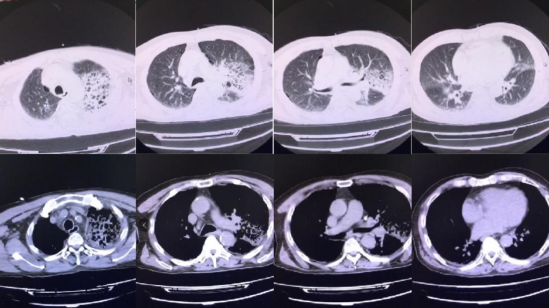

患者男性,64岁,个体户,因“鼻塞、流涕1周,发热2+天”于2021年9月3日入院。患者1周前受凉后出现鼻塞、流涕,无发热、畏寒,无咳嗽、咳痰,自服“阿莫西林胶囊、头孢克肟胶囊、阿奇霉素分散片”后症状未见明显缓解。2天前患者开始出现发热,最高体温39.9℃,伴咳嗽、咳痰,痰为白黏痰,而后逐渐出现双上肢乏力,伴肘关节以下肌肉酸痛,双手指端麻木。于2021年9月2日就诊于当地医院,入院时监测血压波动在76~93/47~52 mmHg之间,完善胸部CT提示:双肺间质性改变并渗出(图1)。血常规提示:白细胞1.50×109/L、中性粒细胞绝对数0.93×109/L,考虑脓毒性休克、重症肺炎并ARDS、MODS,予气管插管+有创机械通气、抗感染等治疗后患者氧合及循环情况未能改善。于9月3日联系我科行VA-ECMO高级生命支持,后为进一步治疗转入我科。患者有痛风病史6年,间断自服药物治疗(具体不详)。

图1 2021年9月2日患者胸部CT可见双肺间质性改变并渗出,左肺为著有高血压病史2年,血压最高180/100 mmHg,平素予硝苯地平片1片qd控制血压,已自行停药2个月。既往无粉尘接触史;无喂养家禽生活史;长期吸烟、饮酒史。T 36.3℃,P 117次/min,R 15次/min(PC模式:PC 12 cmH2O,PEEP 6 cmH2O,R 15次/min,FiO2 40%),BP 96/60 mmHg[去甲肾上腺素3 μg/(kg·min)维持],SpO2 95%。RASS评分-4分。双肺呼吸音减低,可闻及散在湿啰音。心率117次/min,律齐。各瓣膜未闻及明显杂音。双下肢不肿。外院(9月2日)血常规:白细胞1.50×109/L,血小板49×109/L,中性粒细胞绝对数0.93×109/L,淋巴细胞绝对数0.44×109/L;血生化:CK 548 U/L,超敏肌钙蛋白8.48 ng/ml,肌红蛋白1211.79 ng/ml,CK-MB 14.33 U/L,血肌酐330.24 μmol/L,PCT 90.97 ng/ml。BNP 1956 pg/ml。凝血功能:PT 20.6 s,APTT 21.8 s,FBG 6.3 μg/ml,D-二聚体2.22 μg/ml。颅脑+胸部+腹部CT:①双侧基底区腔隙性脑梗灶、缺血灶;②双肺间质性炎症伴多发肺大泡;左肺及右肺下叶多发炎性实变(图1)。入院后查血气分析pH 7.40,PaO2 59.3 mmHg,PaCO2 23.2 mmHg,HCO3- 14.4 mmol/L。心脏超声:①轻度肺动脉高压;②三尖瓣少-中量反流。①重症肺炎并ARDS VA-ECMO辅助;②感染中毒性心肌炎?心脏扩大,心功能Ⅳ级(Killip分级);③多器官功能障碍综合征(心、肺、肾、凝血);④休克(分布性、心源性);⑤原发性高血压3级,很高危组;⑥低蛋白血症;⑦粒细胞缺乏;⑧血小板减少。